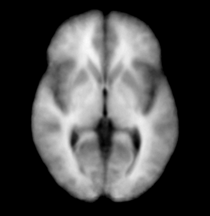

The SUBGM and SUBWM were excluded for the studies done by Nakamura et al, 2007 but were added back to the manually segmented scans and were used in generating the atlases used for our segmentation purposes.

| Manually segmented scan with the subcortical GM and WM structures added. |